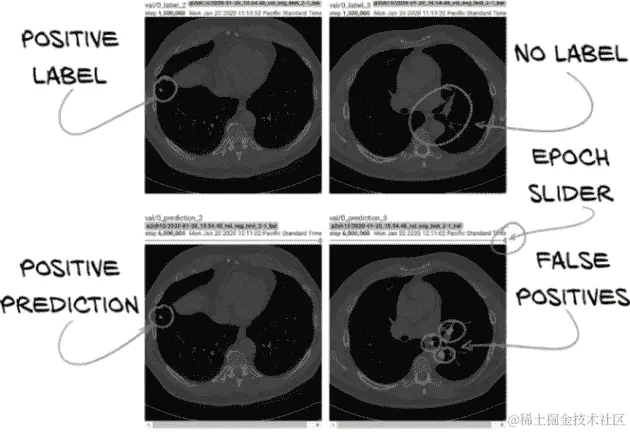

我们没有一种单一正确的方式来构建我们的图像记录。我们将从训练集和验证集中各选取几个 CT 图像。对于每个 CT 图像,我们将选择 6 个均匀间隔的切片,端到端显示地面真实和我们模型的输出。我们之所以选择 6 个切片,仅仅是因为 TensorBoard 每次会显示 12 张图像,我们可以将浏览器窗口排列成一行标签图像在模型输出上方。以这种方式排列事物使得我们可以轻松地进行视觉比较,正如我们在图 13.16 中所看到的。

图 13.16 顶部行:训练的标签数据。底部行:分割模型的输出。

还请注意prediction图像上的小滑块点。该滑块将允许我们查看具有相同标签的先前版本的图像(例如 val/0_prediction_3,但在较早的时期)。当我们尝试调试某些内容或进行调整以实现特定结果时,能够查看我们的分割输出随时间变化的情况是有用的。随着训练的进行,TensorBoard 将限制从滑块中可查看的图像数量为 10,可能是为了避免用大量图像淹没浏览器。